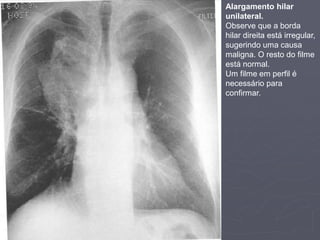

Alargamento hilar unilateral

►Suspeite de alargamento hilar unilateral se:

▪ Um hilo é maior que o outro

▪ Um hilo está mais denso que o outro

▪ Existe uma perda da concavidade normal – os

hilos são geralmente côncavos. Este

concavidade pode desaparecer e ser o primeiro

sinal de alargamento hilar.

►Se você suspeitar de alargamento hilar

então:

▪ Cheque a qualidade do filme. Um filme rodado

fará um hilo aparecer mais largo que o outro.

▪ Olhe para o filme em projeção lateral. Um hilo

alargado pode parecer anormalmente denso na

lateral.

▪ Observe filmes anteriores.

► Para decidir se o alargamento é devido ao

dilatação vascular ou aumento dos linfonodos

hilares ou se é devido ao um carcinoma

brônquico central superposto, observe:

1. A margem do hilo:

1. As margens vasculares são regulares por natureza.

2. Linfadenopatia dá uma aparência lobulada.

3. Espiculação irregular ou de limites imprecisos sugere

malignidade.

2. Presença de cálcio:

1. A presença de material bastante denso (cálcico)

sugere linfadenopatia

3. Observe o resto do Rx:

1. Se vc suspeita de alargamento hilar, então olhe

cuidadosamente para a periferia procurando por

lesões (tumor, TB) infiltração pulmonar (linfangite

carcinomatosa) ou lesões ósseas (metástases).

4. Mediastino:

1. Alargamento hilar maligno pode estar associado a

linfadenopatia mediastinal superior.

Alargamento hilar

unilateral.

Observe que a borda

hilar direita está irregular,

sugerindo uma causa

maligna. O resto do filme

está normal.

Um filme em perfil é

necessário para

confirmar.